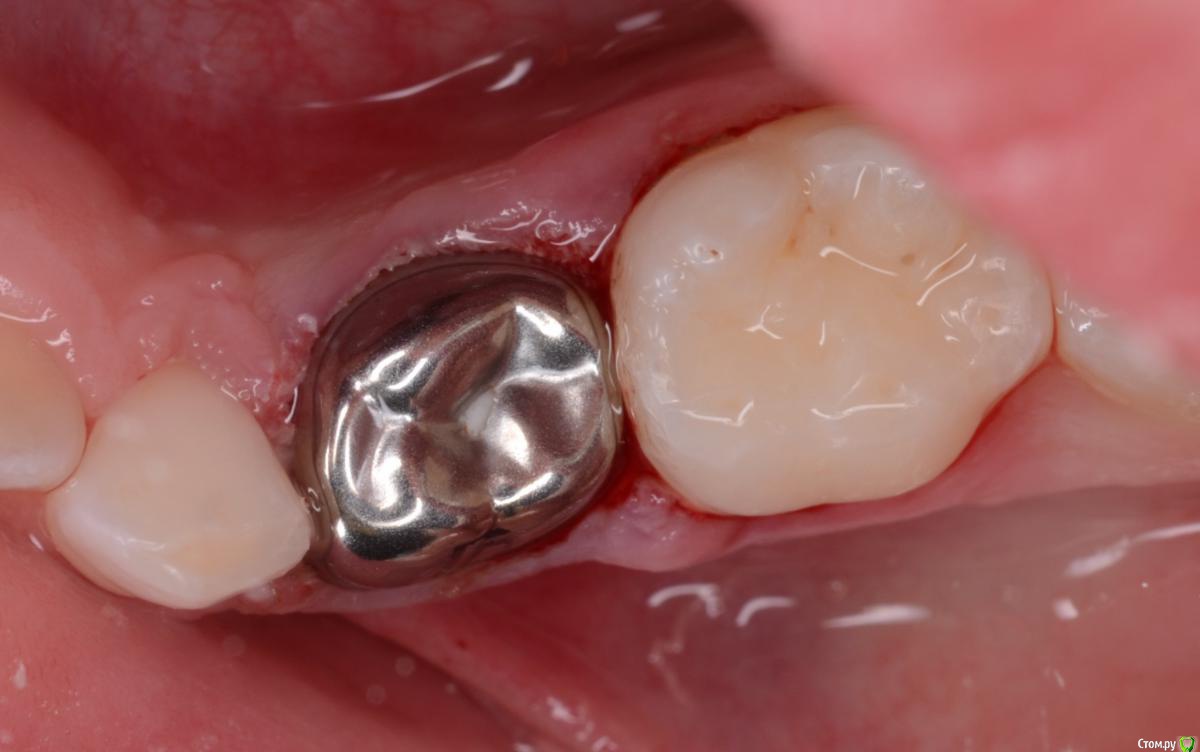

CRAZYDUCK Опубликовано 30 мая, 2018 Автор Поделиться Опубликовано 30 мая, 2018 (изменено) В этом случае немного видно преп под коронку . Описание случая ниже .B9CDEEE8-69F9-4F9D-B72C-1663ADE5EECD.bmp Изменено 30 мая, 2018 пользователем CRAZYDUCK 7 Ссылка на комментарий

CRAZYDUCK Опубликовано 30 мая, 2018 Автор Поделиться Опубликовано 30 мая, 2018 Лечение 7.4 . Необратимый пульпит 7.4 зуба . В данном случае хорошо видно , что после ампутации гемостаз не наступает ( полость зуба заполнена кровью). Позже выложу случай со спонтанным гемостазом . Одного критерия , который бы со 100% вероятностью помогал понять , что нужна экстирпация нет . ❗Жалобы —если была самопроизвольная боль , которая не была связана с приемом пищи или выраженное последействие после пищи, боль купировалась приемом обезболивающего . Болит так , что ребёнок плачет . Самопроизвольная боль есть - скорее всего экстирпация ( если не удаление зуба).❗RVG если полость пульпы сообщается с кариозной полостью , то скорее всего экстирпация - учитывать проекцию тоже нужно .❗Гемостаз должен наступить через 4-5 минут после ампутации, если его нет - экстирпация .В данном случае боль была только кратковременная после приёма жесткой пищи . Преп, экстирпация ( Sxмашинный протейпер ), потом до 25.02 ручными , гипохлорит 3%, Йодотин в каналы , IRM культя , коронка фиксирована на Айрекс Цем . Обратите внимание - во время обработки зуба под Коронку - все в хлам и платок и десна . Предупреждаем родителей о дискомфорте , связанном с травмированием десны. 7 Ссылка на комментарий

CRAZYDUCK Опубликовано 30 мая, 2018 Автор Поделиться Опубликовано 30 мая, 2018 Эстетика в детской стоматологии. Речь о методах лечения , которые влияют на «красоту» зубов. Коронки .Поставила бы я своему ребёнку такую коронку ?! Да, если бы это требовалось для сохранения зуба до смены . Да, они некрасивые и металлические, но функцию сохранения зуба выполнят лучше , чем обширная пломба ( зато беленькая). Срок службы временного зуба ( как правило ) максимум лет 5 -7( больше , если лечили совсем кроху ). Вспомните свои «взрослые» реставрации ( средний срок службы «световой» пломбы 5-7 лет ( если все выполнено в рамках показаний ). Коронки пришли к нам из более развитых стран Европы ( США) , в этих странах коронками покрывают временные зубы уже лет 30( если не больше). Есть Коронки с облицовкой ( но это дороже из-за себестоимости коронок), в будущем будут у нас на приеме и белые Коронки . 4 Ссылка на комментарий